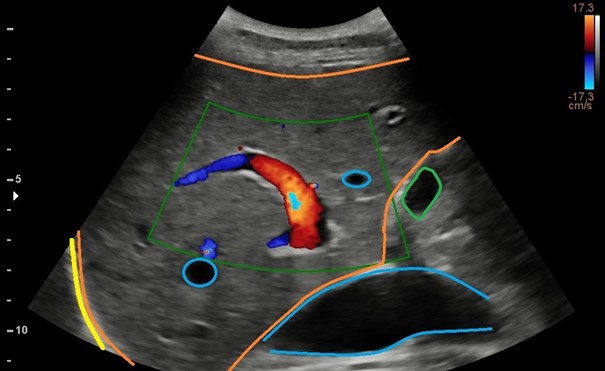

Portale Hypertensie

De vraag naar echografie in het kader van portale hypertensie groeit. Is de richting van de flow in de vena porta alleen bepalend om hierin een uitspraak te doen. Het antwoord is nee!

Tegenwoordig kunnen met de echografie veel meer ten aanzien van de tekenen van portale hypertensie. Ik heb daarvoor een richtlijn ontworpen die gedoceerd wordt op de Post-HBO echografie aan de Inholland Academy.